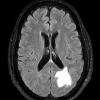

Astrocytoma, IDH-mutant, WHO Grade 2 (3)